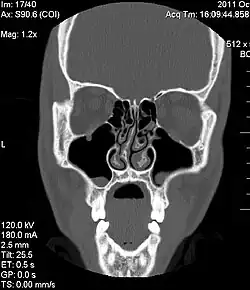

Die Diagnose einer Septumdeviation wird mittels äußerer Inspektion der Nase, vorderer Rhinoskopie, Endoskopie oder Computertomografie (CT) gestellt. Wie stark eine Septumdeviation die Nasenatmung behindert, kann mithilfe einer Rhinomanometrie gemessen werden. Außerdem sollte eine Riechprüfung durchgeführt werden.